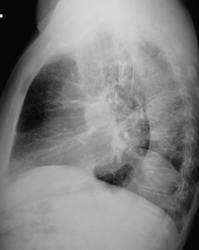

Мнение моё о центральном раке слева.Смещение средостения да кругляш в боковой.

Центральный рак - средостение смещено, тень в проекции левого корня, купол диафрагмы высоко, снижение прозрачности левого легочного поля

Вот суто по прямому снимку высказывался бы за кистозную гипоплазию левого легкого. Но учитывая бок... не совсем подходит. Рак. А может и то, и другое. КТ. А сколько лет пациенту, анамнез?

Насколько я понимаю, круглая штучка оказалась в правом корне, тогда кто его знает что это такое

не очень характерно для дисплазии. Думается все смещения, элевации, псевдоателектазы обусловлены этим.